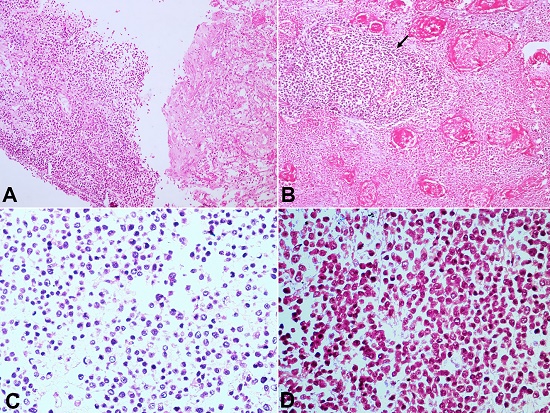

A new CT-guided biopsy was attempted and showed atypical cells consistent with an underlying malignant lesion (Figure 2A). The thoracocentesis revealed an exudative and hemorrhagic pleural effusion without malignant cells.

Histological examination of the lung depicted tumor cells in cohesive sheets, having a peritheliomatous arrangement amidst predominantly necrotic areas. The tumor cells were round to oval, had coarsely stippled chromatin with scant to mildly eosinophilic cytoplasm. Nucleoli were inconspicuous, and mitosis was brisk. Numerous apoptotic bodies were also noted (Figure 22C).

IHC reactions showed the tumor cells to be diffusely positive for Vimentin (strong cytoplasmic positivity), CD99 (strong membranous positivity), and FLI 1(strong nuclear positivity). The tumor cells were diffusely negative for calretinin, WT1, D240, synaptophysin, CD56, TTF1, Tdt, S-100, desmin, myogenin, BCL-2, LCA, and EMA. On Periodic Schiff stain (PAS), the cytoplasm of tumor cells showed strong magenta cytoplasmic positivity (Figure 4AD). Sections from the left upper and lower lobe showed normal air-filled alveoli lined by type II pneumocytes.